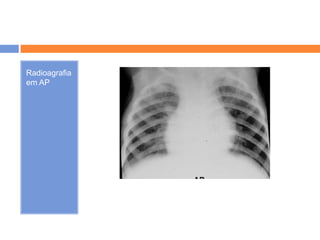

Radioagrafia

em AP

   Perfil  não se visualiza a linha associada ao

AD